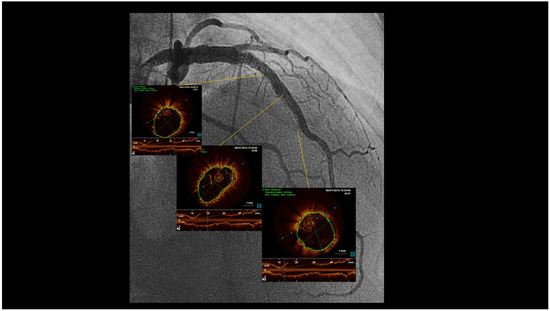

When performing revascularisation of a chronic total occlusion, contralateral injection is essential to visualise the distal bed of the occluded vessel, adding to procedural success. Here we describe a case of antegrade recanalisation of a left anter...